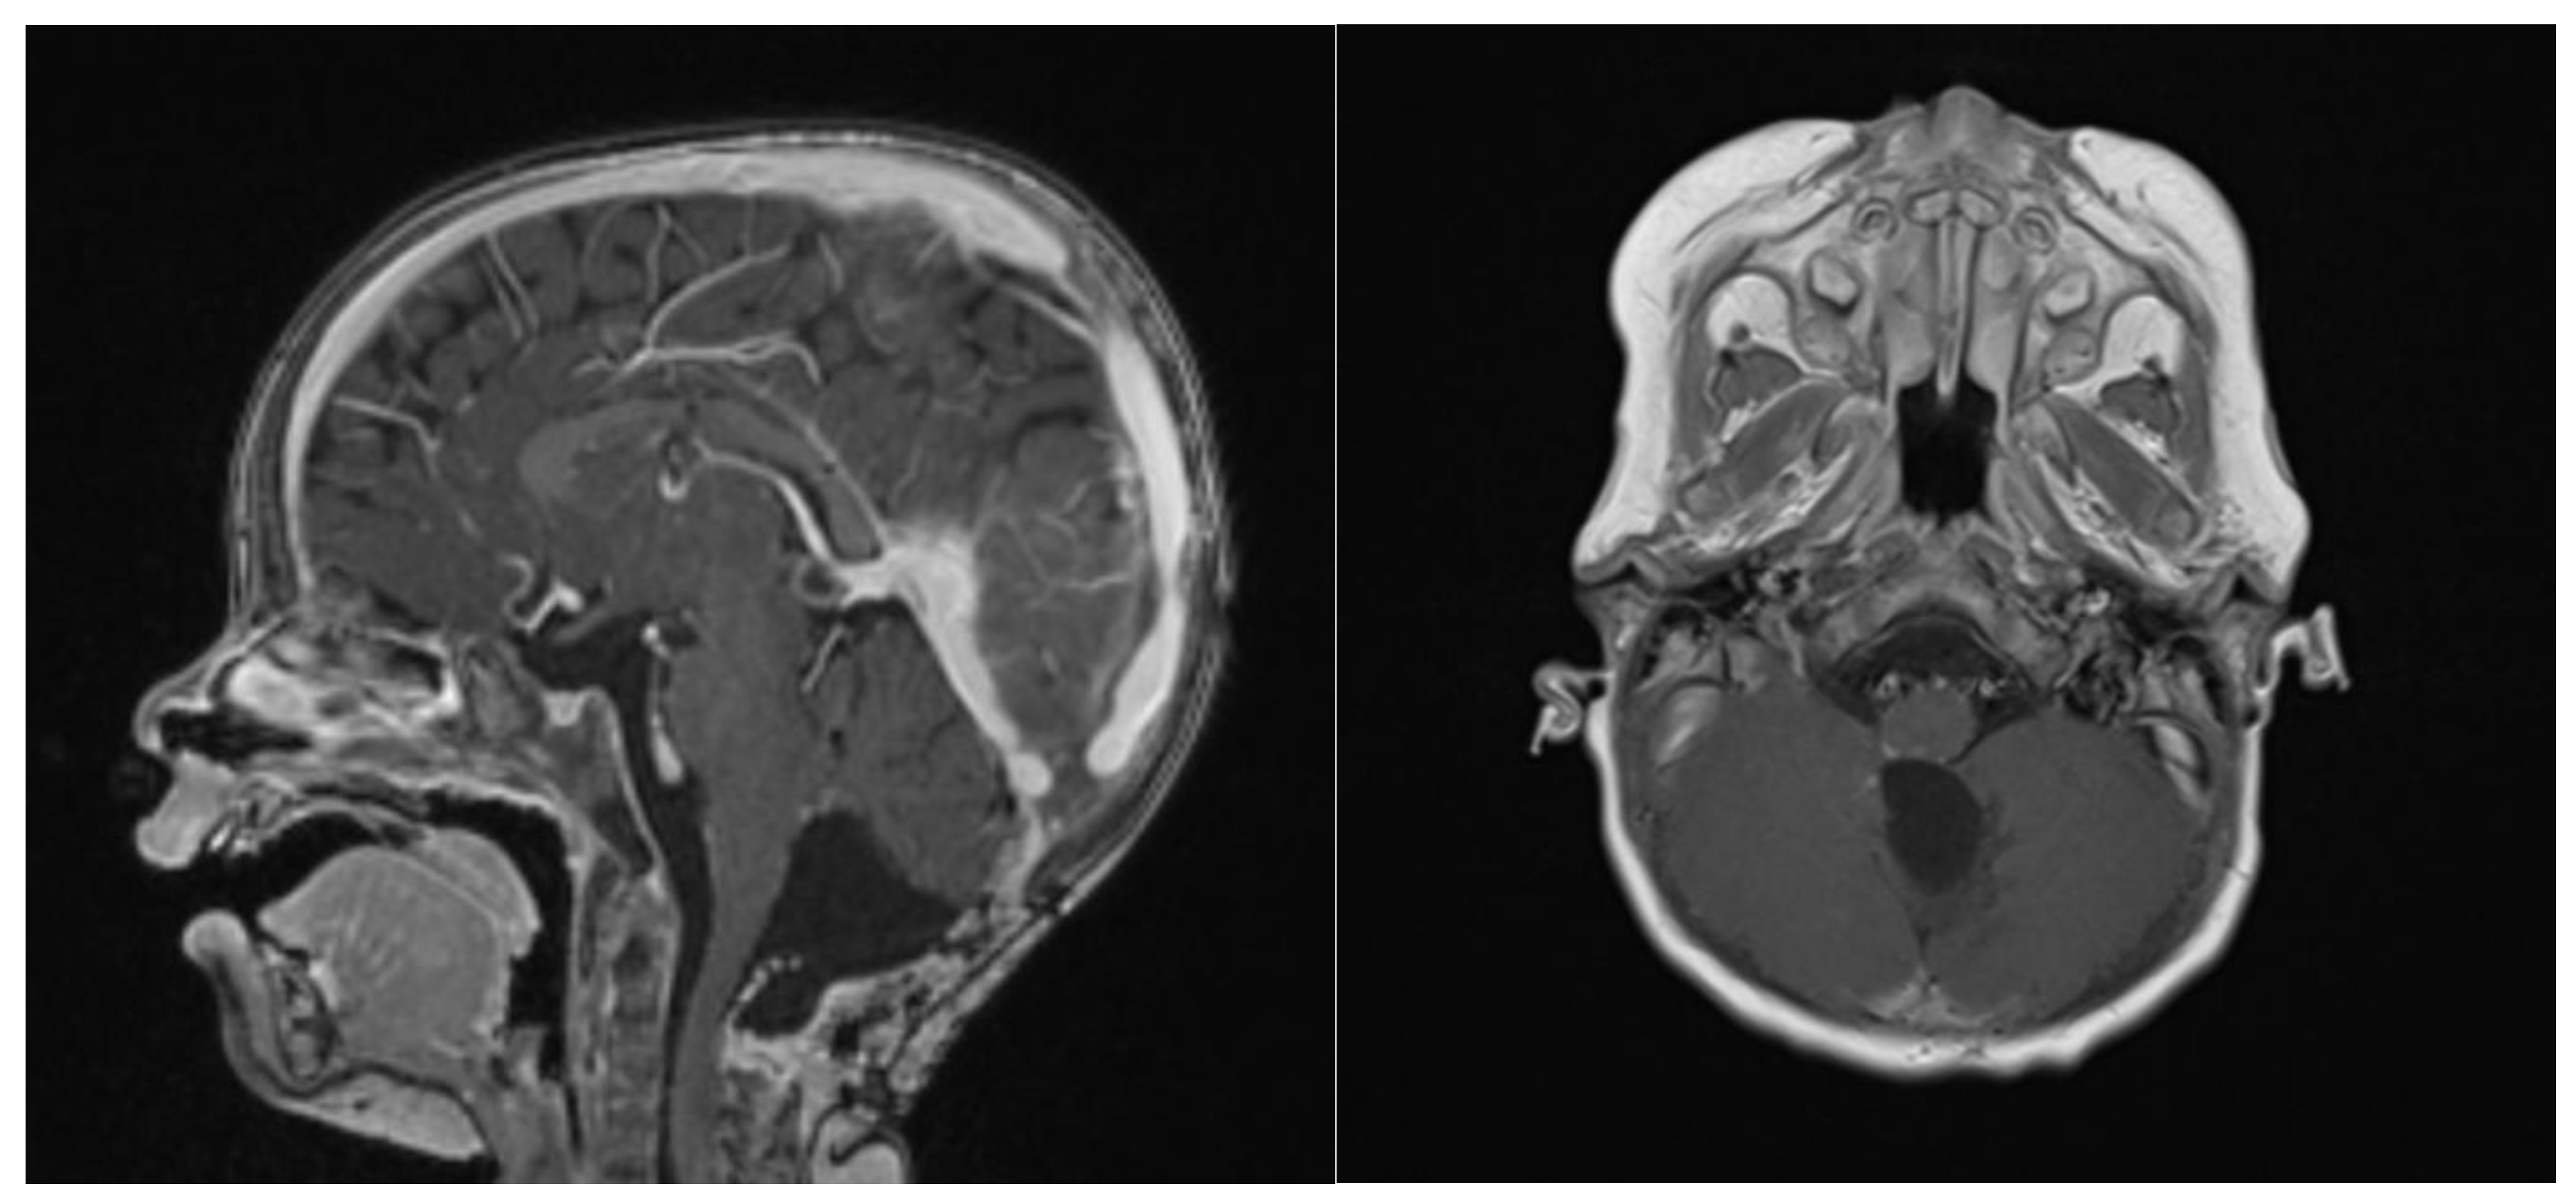

At 6 weeks after starting induction chemotherapy (after 3 courses of induction chemotherapy), craniospinal MRI showed a partial response to the treatment, with a >50% volume shrinking and no leptomeningeal dissemination, as assessed by an experienced senior neuroradiologist consultant (Figure 5). Considering the tumor volume reduction and the good general condition, a second-look surgery was offered in an attempt to achieve a GTR.

Figure 5.

Gadolinium T1 MR sagittal and axial sequences at 6 weeks post-chemotherapy induction. ATRT volume diminished from 43.7 cm3 to 16.6 cm3.